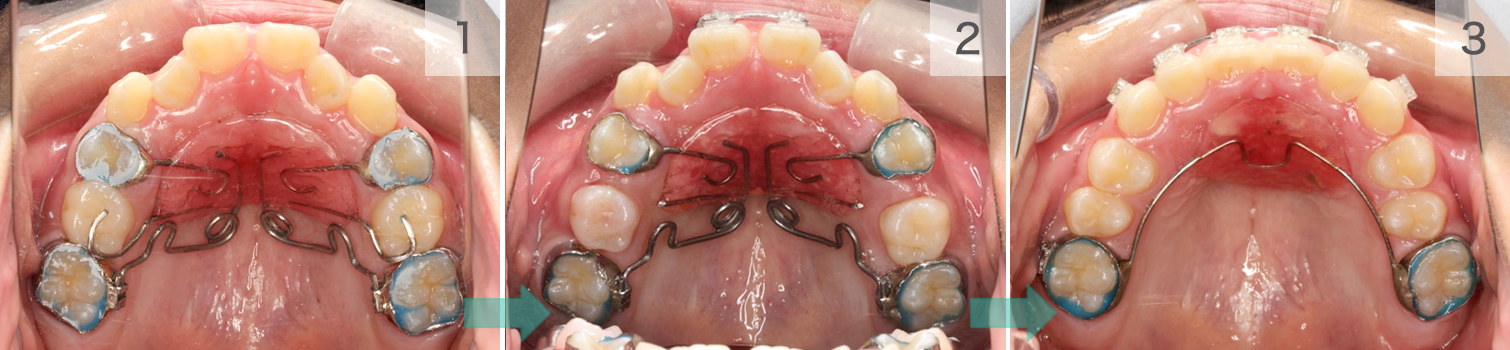

症例08. ペンデュラム

パラタルパッドと上顎小臼歯を固定源として上顎大臼歯を遠心移動させる装置。

取り外しできませんが、毎回Drが調整します。

| 治療内容 | 1:上顎大臼歯をワイヤーの弾性力で遠心へ送る 2:スペースが生まれているのが確認できる 3:スペースを使って前歯の凸凹を並べる |

|---|---|

| 期間 | 半年~2年 |

| 費用 | 300,000円+税 |

| リスク | 磨きづらい箇所は虫歯になるリスクが あります。 |